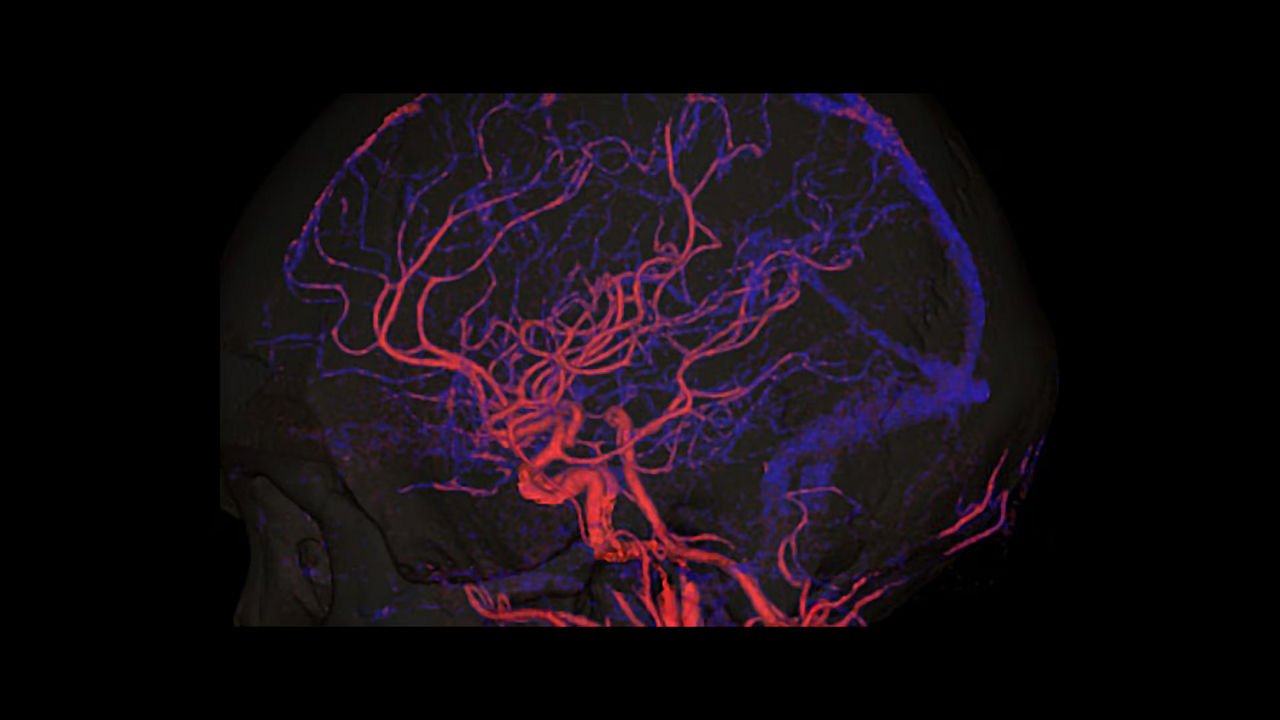

Simplify the Stroke CT workflow and the communication within the stroke team.

<p>FastStroke with StrokeSENS<sup>3</sup></p>

Learn more

<p>CT Perfusion 4D Neuro</p>

<p>Dynamic Shuttle</p>